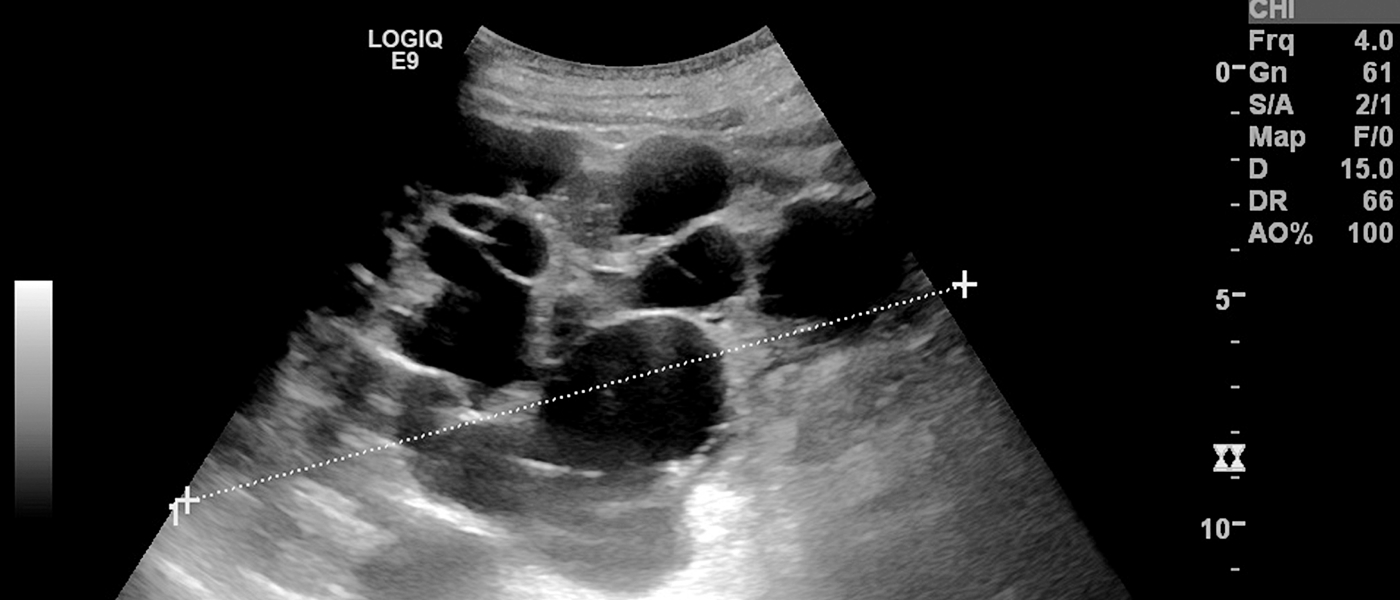

신우신염(신장 감염), 신장결석, 만성신부전, 신낭종 등이 주요 질환입니다.

요로 흐름이 막히거나 비정상이면 신장 기능이 저하되고 장기적으로 만성질환으로 이어질 수 있습니다.